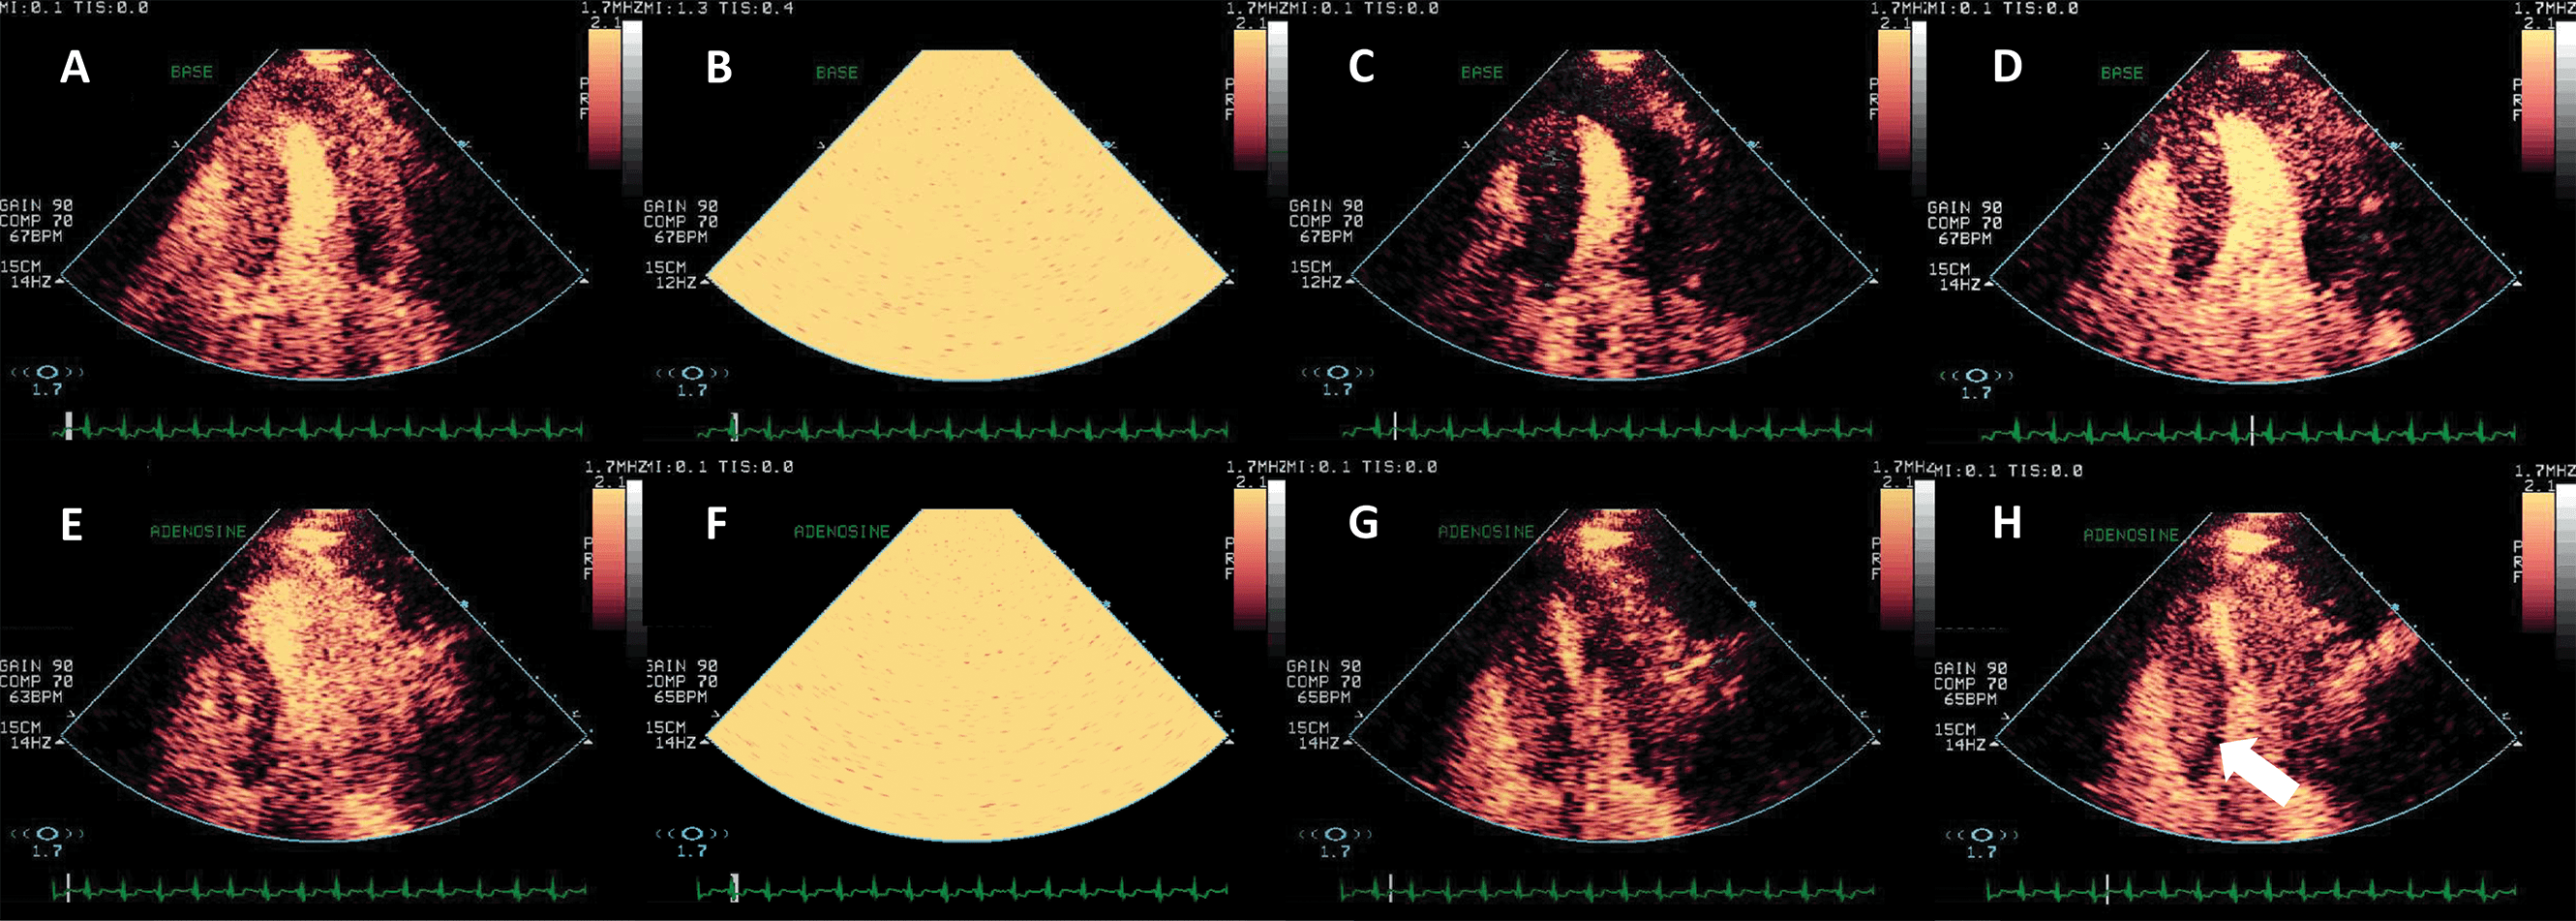

UEA have largely been used in the detection of LV thrombi [76, 77, 78]. This is in fact an application of the LVO method, enhancing the delineation between the wall, cavity and the thrombus mass (Fig. 10, Ref. [79]). However, prognostic implications for small mural thrombi are not clear. Myocardial perfusion detection, as described above, may help to diagnose small intracardiac or even intramural masses, by the presence and the dynamics of the vascularization inside the mass [80]. By adding a quantitative approach, it may even be possible to differentiate not only thrombi from tumors, but also benign from malignant tumors [79] (Fig. 11, Ref. [79]).

Fig. 10.Detection of an apical thrombus in a patient with severely depressed EF. Native images in apical 4 (A) and 2 chambers (B) do not demonstrate the presence of an apical mass. (C) 3D contrast-enhanced echocardiography demonstrating an apical filling defect (thrombus-arrows). (D) Apical 2-chambers 2D contrast-enhanced image, the thrombus is present in the apical LV. Images modified with permission from Strachinaru et al. [79].

Fig. 11.Hyperechoic and hypermobile mass in a normal LV. The image quality is good, and the mass is hyperechoic. (A) 4-chambers view. (B) 2-chambers view. (C) Signal intensity quantification after a flash-replenishment cycle. The replenishment of the mass is similar to the interventricular septum, but with higher intensity, signalling the presence of a capillary vascularisation, with a higher density than the myocardium. (D,E) Parametric map of signal intensity, demonstrating the same features of the mass. In this patient the mass was finally diagnosed as a hypervascular metastasis from a lung carcinoma. Images modified with permission from Strachinaru et al. [79].